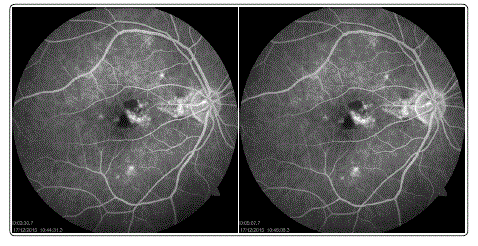

Upon doing FFA, we observed presence of a group of polypoidal vessels in an avascular area in the macular region. A small vascular leak was also observed in the region of the polypoidal vessels. OCT showed an increase in thickness in the macular region.

Figure 3: FFA images at different time intervals.